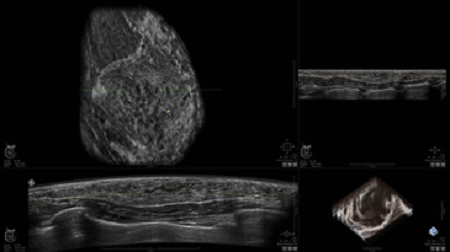

• Получение объемных 3D изображений с возможностью покадрового просмотра

• Отображение объемных 3D ультразвуковых изображений, которые состоят из традиционных поперечных и воссозданных коронарных и сагиттальных проекций

• Возможность отображения полного 3D изображения

• Стандартизованная ориентация изображения: «толстый срез» в коронарной плоскости; поперечная; сагиттальная плоскость; радиальный и антирадиальный поворот изображения; просмотр исключительно области интереса

• Изменяемая толщина среза: 0,5 - 10,0 мм (шаг 0,5 мм)

• Срез: 0,5 - 2,0 мм (шаг 0,5 мм)